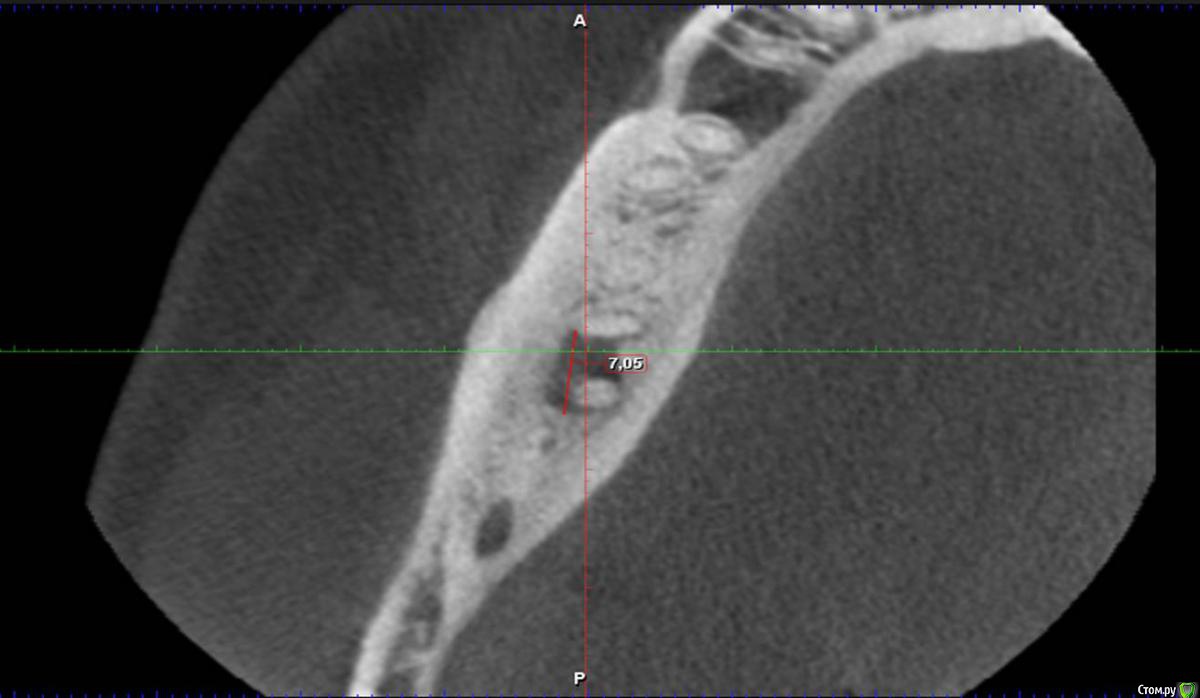

Сева северный Опубликовано 21 апреля, 2016 Поделиться Опубликовано 21 апреля, 2016 (изменено) .Хотелось бы выслушать мнение по зубу 4.6Пациент пришел по рекомендации, коллеги, из сторонней клиники. . Как бы вы поступили в данной ситуации? ( Скриншоты КТ, прилагаются) Изменено 21 апреля, 2016 пользователем Сева северный Ссылка на комментарий

Сева северный Опубликовано 21 апреля, 2016 Автор Поделиться Опубликовано 21 апреля, 2016 (изменено) Мужчина. Возраст: около 50,Жалобы. на болевые ощущения ..отсутствуют. Зуб ранее лечен, имеется старая пломба с нарушенным прилеганием, по границам- кариес. Пальпация, перкуссия безболезненна, в области бифуркации при надавливании, появляется жидкость, желтоватого цвета. При зондировании зонд погружается в межкорневое пространство примерно на 15 мм. Изменено 21 апреля, 2016 пользователем Сева северный Ссылка на комментарий

Сева северный Опубликовано 26 апреля, 2016 Автор Поделиться Опубликовано 26 апреля, 2016 Пошаманили .... через 3.5 месяца. Ссылка на комментарий

Сева северный Опубликовано 27 апреля, 2016 Автор Поделиться Опубликовано 27 апреля, 2016 (изменено) Это надо в Вк запостить, для удаляторов)Да там такого много. Вопрос удаления. конечно рассматривался... Но для имплантации, потеря зоны костной перегородки в зоне бифуркации, достаточно критична. Поэтому.. приняли решение эндосанации . (повыращивать кость), а в случае успеха обойтись без нее. Как показывает практика, большие очаги, особенно если не ступала ((((нога стоматолога , с гипохлоридом, быстро... схлопываются. Изменено 27 апреля, 2016 пользователем Сева северный 2 Ссылка на комментарий